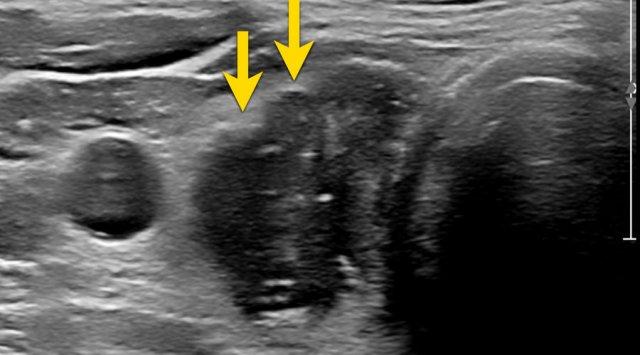

Nốt với Bờ Không Đều, Góc Cạnh

Nốt này có bờ không đều, góc cạnh.

Điểm TI-RADS: 2 điểm.